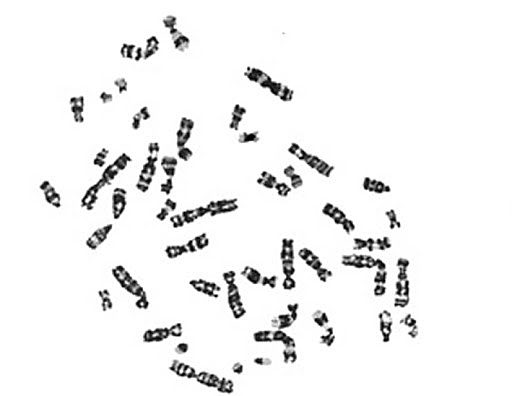

Año 1956

Tjio, Levan establecieron que el número

cromosómico humano era de 46.